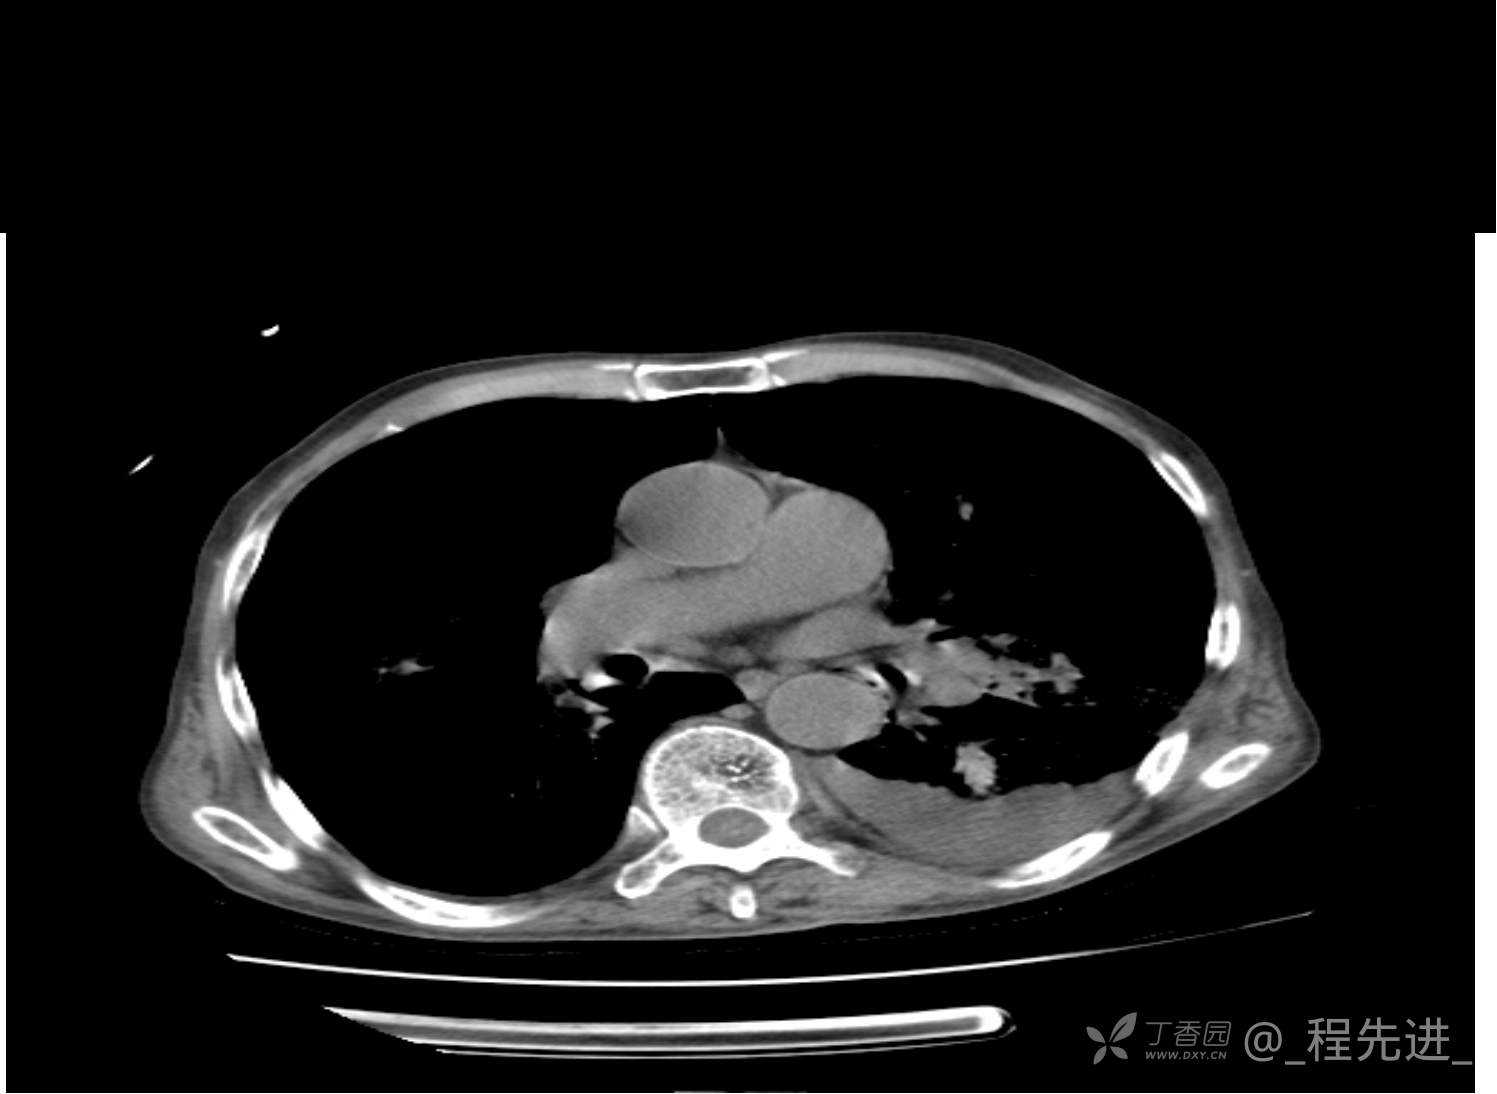

患者性别:男

患者年龄:81岁

简要病史:反复咳嗽、咳痰20余年,加重1周。两肺呼吸音低,可闻及散在干湿啰音。